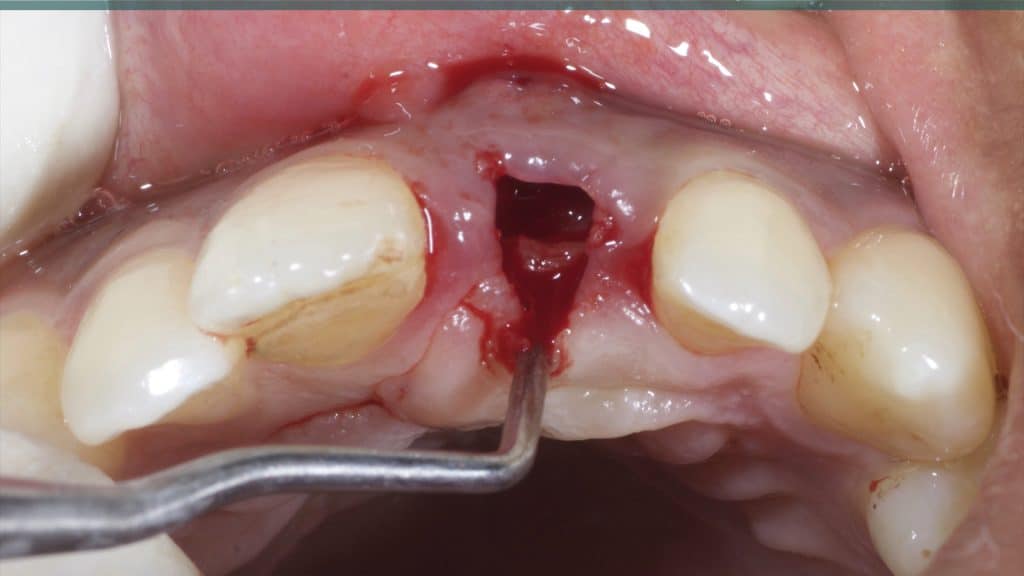

A 27-year female patient with dislodged Resin bonded FPD. She had that FPD for past few years, it had metal wings on palatal surfaces of UR1 and UL2 and a post like metal extension into the root canal of UL1. There was gingival abscess due to fractured root segment most probably due to extended metallic post like structure. Immediate implant placement (IIP) and Immediate restoration (IR) was planned for this patient.

Occlusal check